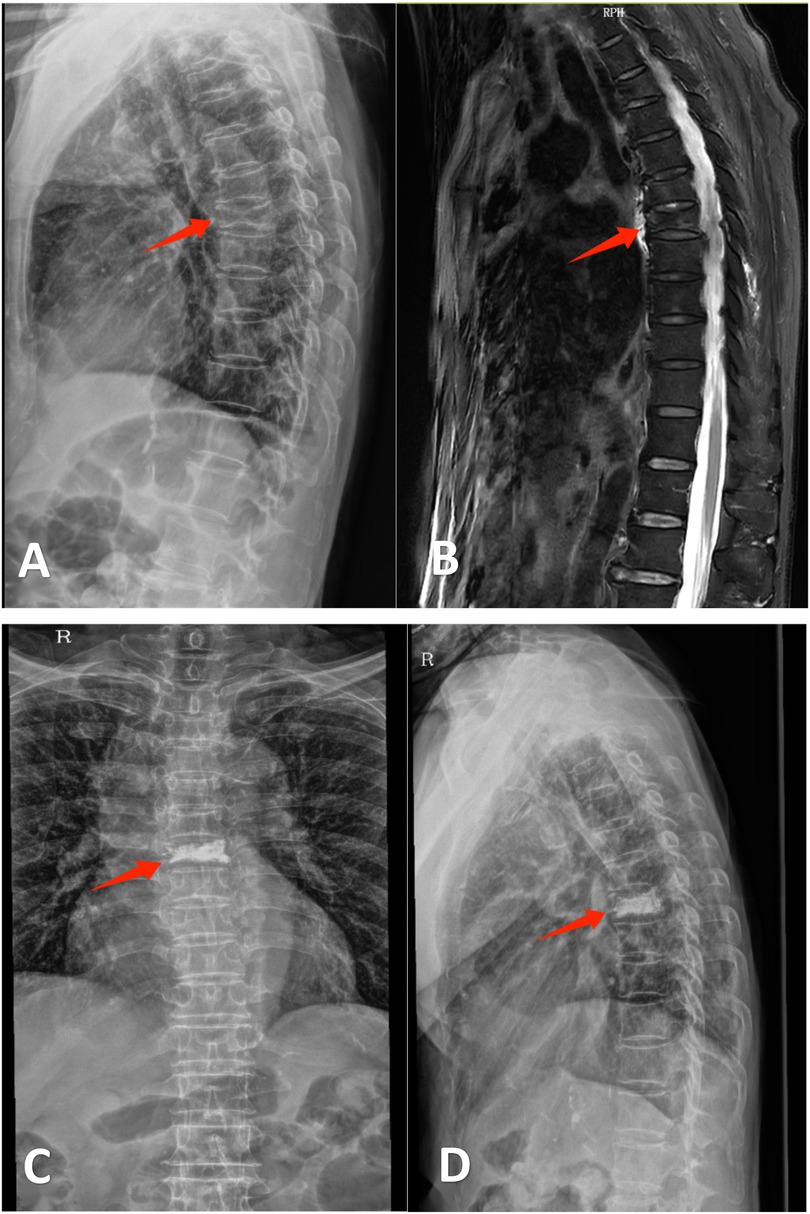

For DSP group patients, a definitive diagnosis was established during outpatient evaluation with the completion of all preoperative imaging and laboratory tests. One-day admission was arranged for surgical intervention on the day of hospitalization. TIP group patients underwent preoperative workup after hospital admission. Both cohorts underwent PKP procedures under local anesthesia with monitored anesthesia care (MAC), following standardized surgical protocols (14) (Figures 1, 2).

Figure 2. Ms. Zhou, a 76-year-old female, was admitted for “thoracic back pain persisting for 4 days following a twisting injury.” Diagnosis: T6 vertebral compression fracture. She underwent unilateral percutaneous kyphoplasty (PKP). Postoperative pain was significantly alleviated, thus permitting same-day discharge. (A) Lateral radiograph demonstrating wedging deformity of the T6 vertebral body. (B) Sagittal MRI revealing a T6 vertebral fracture. (C,D) Postoperative anteroposterior and lateral radiographs after unilateral PKP at T6.